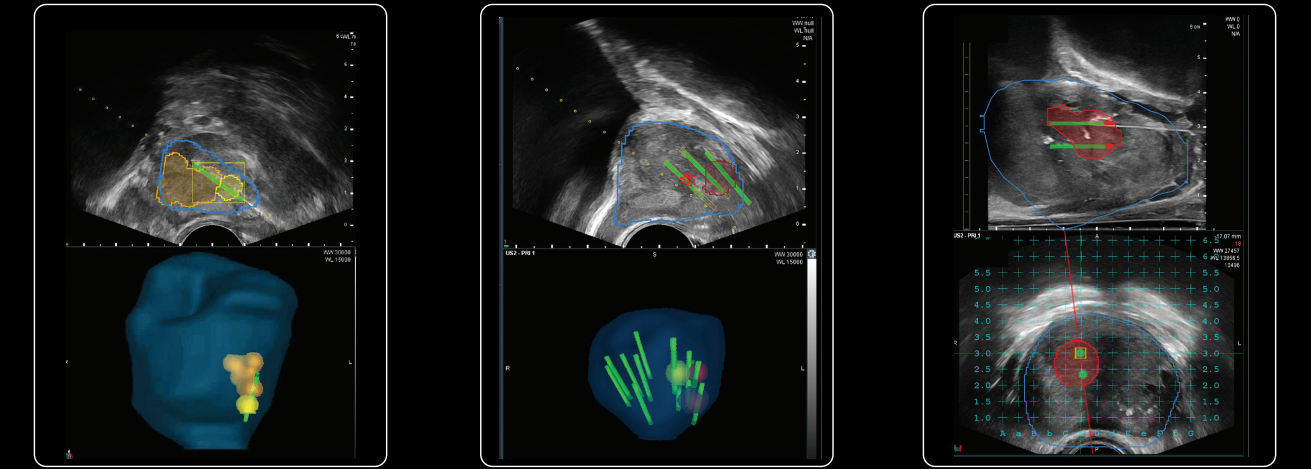

Segundo ele, a fusão que usa a tecnologia bkFusion de imagens melhora significativamente a precisão do procedimento, aumentando as chances de detecção de lesões em áreas suspeitas.

A fusão free-hand, com uso do ultrassom, que utiliza o software de última geração bkFusion, é considerada mais segura para o paciente também por conta do acesso feito por via perineal. Outra vantagem, a de maior eficácia nos resultados, é oriunda da fusão de imagens entre o ultrassom e a ressonância magnética (RMN).

“Através da fusão de imagens da Ressonância Magnética realizada pré procedimento, com a imagem do ultrassom em tempo real, conseguimos garantir maior precisão e assertividade quando necessitamos de biopsiar uma região lesionada específica da próstata, explica Bruno Cordeiro, Especialista de Produtos da Strattner, destacando as vantagens para os profissionais que realizam o procedimento.